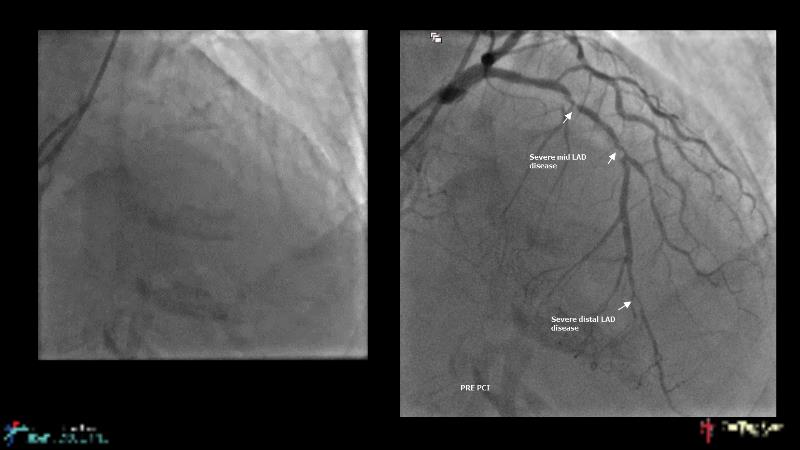

A hybrid approach in complex PCI: can DES and DCB be complementary?

Watch this case-based session to follow discussion about how to choose between DES & DCB, how both can be complementary in diffuse disease as well as in complex PCI, and how physiology and imaging can help guiding PCI, and follow a patient's treatment live.